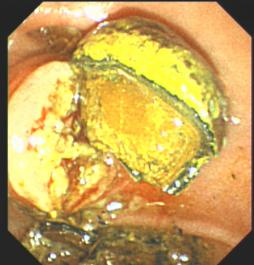

胆石症ERCP治疗